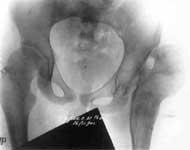

1.Врожденный вывих левого бедра.